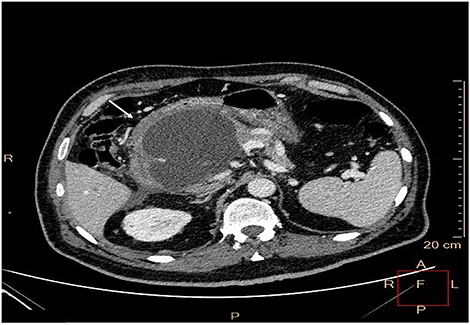

Upper abdominal magnetic resonance imaging, magnetic resonance cholangiopancreatography (Fig. 1) and contrast-enhanced computed tomography (CT) (Fig. 2) revealed large walled-off pancreatic necrosis in the pancreatic head, measuring 10.5 × 6.5 × 9 cm, compressing the inferior vena cava, the common bile duct and the duodenum. There were also peripancreatic pseudocysts, with the biggest measuring at 12.5 cm.

Contrast-enhanced CT. Large walled-off pancreatic necrosis in the pancreatic head, pressing inferior vena cava and duodenum (white arrow).